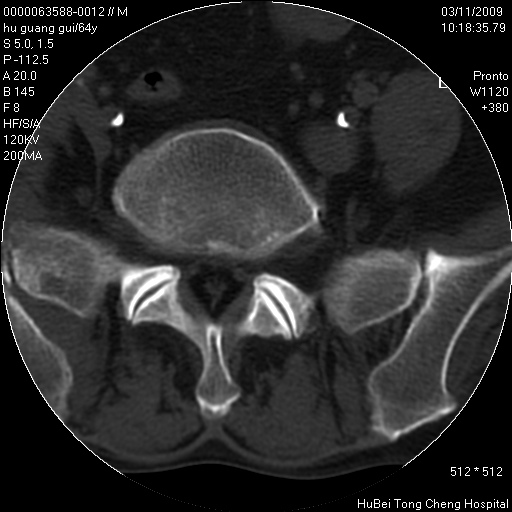

患者 男,64岁。腰痛十余天。(临床未提供其他病史)

临床诊断:腰痛原因待查(腰椎间盘突出症?)。

腰椎间盘ct轴位平扫(层厚5mm,层距4mm),图像如下:

腰椎退行性变,腰4—5椎间盘膨出。

右侧骶骨侧块骨侵蚀,骶髂关节骨性关节面破坏,并见软组织肿块,考虑骨转移瘤可能,进一步检查。

1.腰椎退行性变,腰4—5椎间盘膨出。

2.右侧骶骨侧块骨侵蚀,骶髂关节骨性关节面破坏,并见软组织肿块,考虑:脊索瘤,骨转移瘤可能,进一步检查。

1)腰椎退行性变,l4—5椎间盘膨出。2)骶骨右侧块骨转移瘤可能,3)水平骶椎。建议作一步检查。